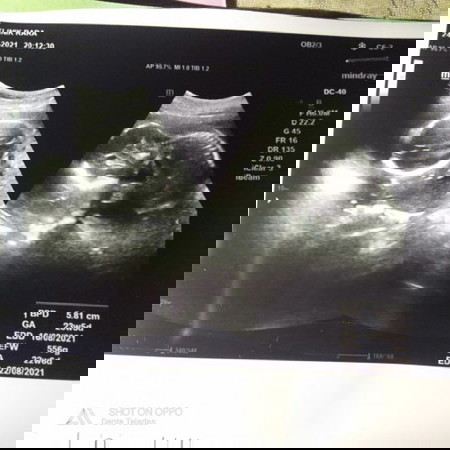

Bingung...perkiraan lahir menurut http 8desrmber,tpi liat hasil usg,,hpl nya 22agustus

saya liat itu usg nya udh dri bulan 4 ya bun.. coba usg lagi pastiin bun... atau bunda lupa hphtnya tgl berapa bun? soalnya jauh banget. .

coba usg lagi bun, itu kan udah 4 bulan yg lalu, lagipula kalau mau ngitung hpl ya dari tanggap hpht kalau ega ya usg tm1